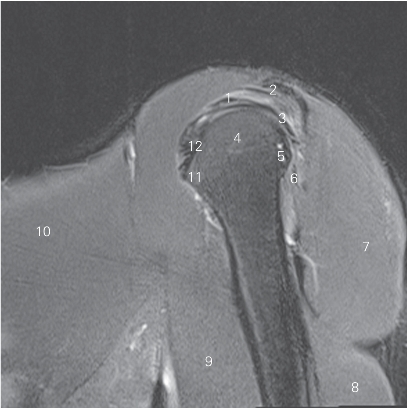

图4-19 经肩峰的矢状断层MR T2WI FS

1 冈上肌 supraspinatus 2 肩峰 acromion

3 冈下肌 infraspinatus 4 肱骨头 head of humerus

5 肱骨大结节 greater tubercle 6 小圆肌 teres minor

7 三角肌 deltoid 8 肱三头肌 triceps brachii

9 肱二头肌 biceps brachii 10 胸大肌 pectoralis major

11 肱骨小结节 lesser tubercle 12 肩胛下肌 subscapularis